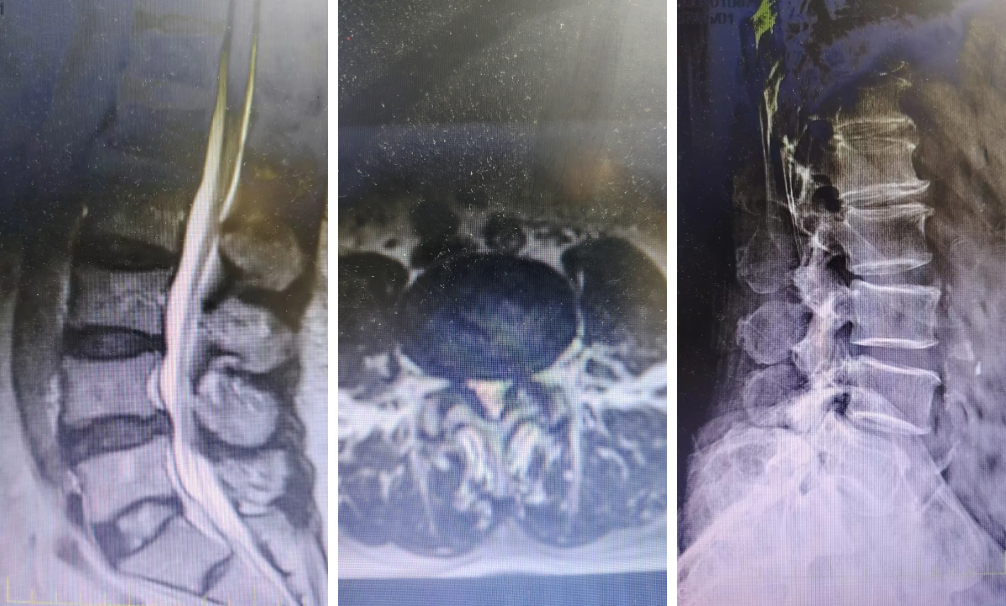

术前

此次接受手术的患者梁先生,68岁,因长期腰背部疼痛伴下肢放射痛、麻木,且行走能力受限,经保守治疗效果不佳后慕名就诊。入院后患者完善腰椎X片、CT、MRI等影像学检查,明确诊断为“腰椎滑脱、腰椎椎管狭窄”,病情已严重影响日常生活与工作。

考虑到患者病情特点及对微创治疗的需求,骨科团队进行了充分的术前评估与病例讨论。传统开放手术虽能解决问题,但存在创伤大、出血多、恢复慢等不足,尤其对合并基础疾病的患者风险较高。而UBE技术作为新兴的脊柱微创技术,通过单侧建立两个1厘米左右的通道——分别作为观察通道和操作通道,可在清晰内镜视野下完成精准操作,且不受器械尺寸限制,操作空间更大,效率更高。最终团队决定采用“UBE腰椎管减压椎间融合经皮内固定术”这一先进方案。